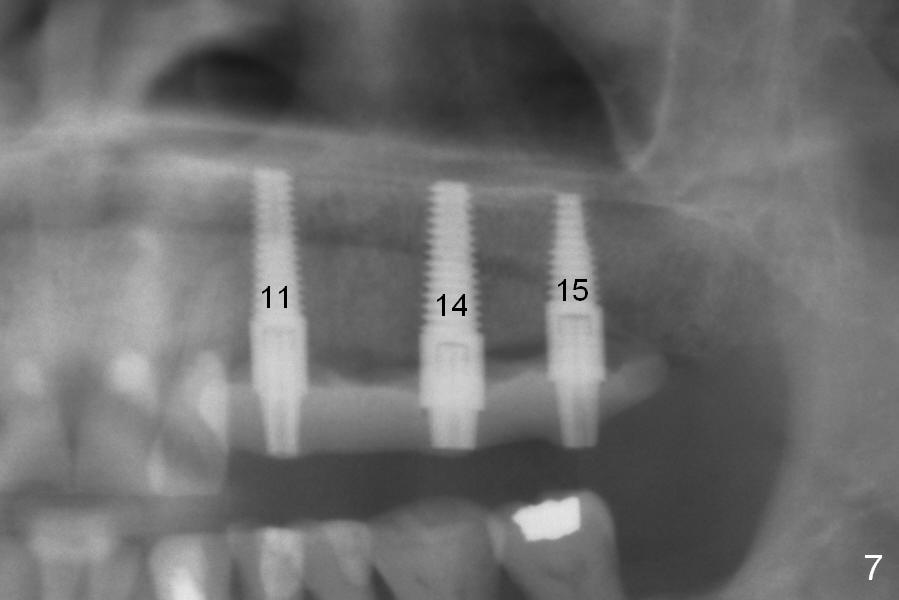

The edentulous ridge distal to #11 residual root is moderately atrophic (Fig.1). The ridge is split with 10 and 13 mm saws between initial osteotomies at #12,14 and 15 (Fig.2). Parallel pins are inserted for trajectory confirmation (Fig.3,4). The gap of the split ridge between #12 and 14 increases when bone expanders (2.7/3.6 mm) are being inserted. A 4.5x17 mm implant does not obtain primary stability at #12. When a 5x17 mm implant is being placed at #12, the buccal plate starts to crack. When the same implant is placed at #14, the crack appears to get larger. Drills are used to finish osteotomy at #14 with force being applied palatally. When the implant is re-inserted, the buccal plate fractures does not appears to get worse (Fig.5 <). In contrast, there is no obvious increase in the gap between #14 and 15 when bone expanders are being used at #15. To avoid complication, drills are used to finish osteotomy before placing a 4.5x14 mm at #15 (Fig.7 (#11: 4.5x17 mm)). CBCT shows that the bone density at #12 and 14 (400-500 Hounsfield units (HU)) is higher than that at #15 (200-300 HU). Ridge split is successful when HU is <200 with smaller diameter implants.